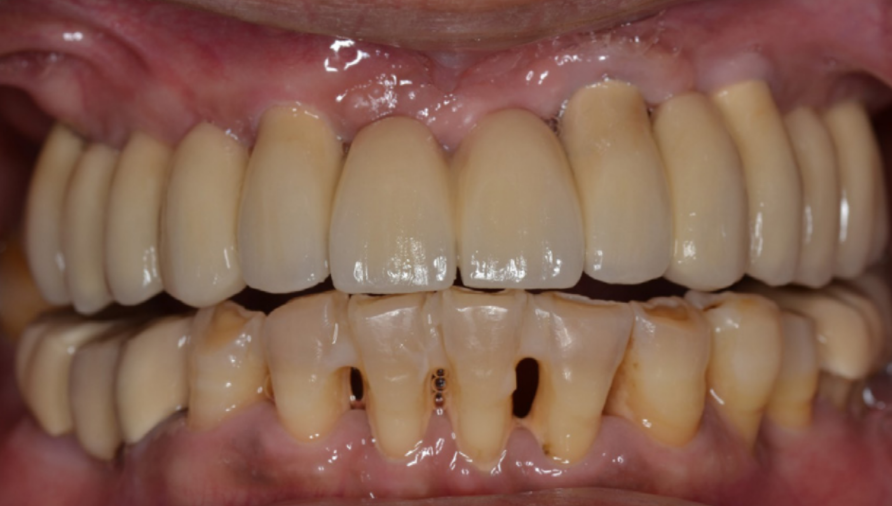

Суцільний металокерамічний протез на цементній основі, закріплений на абатментах Straumann synOcta було нарешті встановлено. (зображення 16)

16